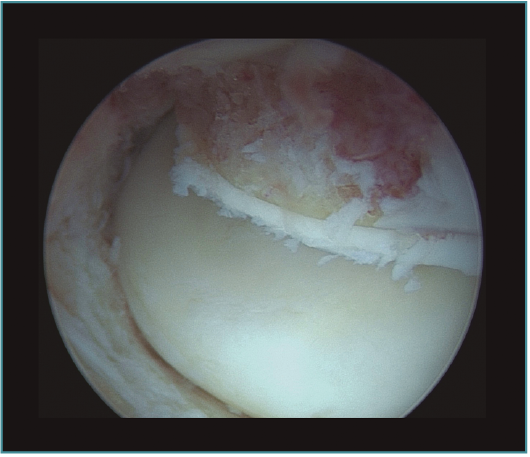

Método: hemos revisado 38 pacientes con codo rígido postraumático o degenerativo que se trataron mediante artrolisis artroscópica entre 2013 y 2016, con un seguimiento medio de 25 meses (38-15). Según la etiología de la rigidez, clasificamos a los pacientes en 2 grupos: grupo 1, los pacientes con rigidez por patología degenerativa del codo, y grupo 2, los pacientes con rigidez postraumática. Clasificamos la rigidez siguiendo la escala de Morrey y utilizamos la escala funcional Mayo Elbow Performance Index (MEPI), que evalúa el dolor, la movilidad, la estabilidad y la función del codo pre- y postoperatoriamente. Describimos los procedimientos artroscópicos realizados en cada paciente, que incluyen la sinovectomía, el desbridamiento de tejido fibroso, la capsulectomía anterior y/o posterior, la resección de osteofitos en la parte anterior y posterior del codo, la extirpación de cuerpos libres y la liberación “abierta” del nervio cubital.

Method: a review was performed on 38 patients with stiff elbow due to degenerative or post-traumatic reasons, and who were treated by arthroscopic arthrolysis between 2013 and 2016, with a mean follow-up of 25 months (38-15). Elbow stiffness was classified following the Morrey scale and the Mayo Elbow Performance Index (MEPI) functional scale was used to evaluate pain, mobility, stability and elbow function pre- and post-operatively. The arthroscopic procedures performed on each patient are described, including synovectomy, debridement of fibrous tissue, anterior and/or posterior capsulotomy, resection of osteophytes in the anterior and posterior part of the elbow, extirpation of loose bodies and open release of the ulnar nerve.